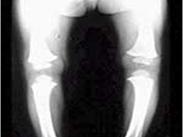

維生素D缺乏性佝僂病,又叫骨軟化癥即骨礦化不足,為新形成的骨基質鈣化障礙,是以維生素D缺乏導致鈣、磷代謝紊亂和臨床以骨骼的鈣化障礙為主要特征的疾病,維生素D是維持高等動物生命所必需的營養素,它是鈣代謝最重要的生物調節因子之一。維生素D不足導致的佝僂病,是一種慢性營養缺乏病,發病緩慢,影響生長發育。多發生于3個月~2歲的小兒。